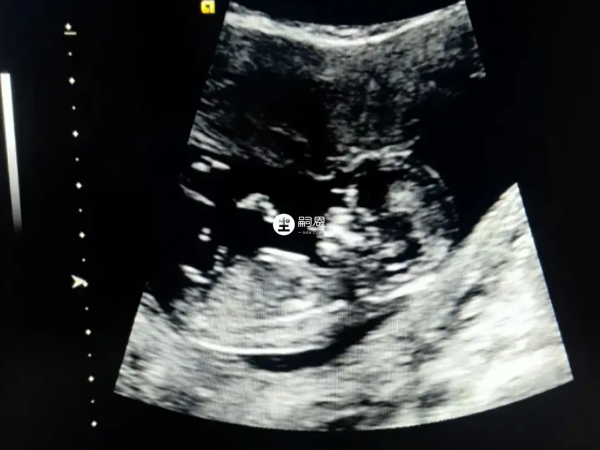

準媽媽們可以在懷孕兩個月的時候到醫院去做B超檢查,如果寶寶的形狀是長型的,或者像茄子的形狀,那麼很有可能是懷男寶寶,如果是橢圓或是圓形,那麼可能是懷女寶寶。

在B超檢查單上,男寶寶的性別特徵比較明顯,常常“凸起的東西”是特有的標誌,在做B超的時候可以看到胎兒生殖器官這裡,如果有小小的突起的話,生男寶寶的可能性較大,相反,生女寶寶的可能小較小。

大家可以看到圖中女寶的生殖器結構,上面有類似於線條的一槓,這就是女寶胎兒的外生殖器結構,有的時候b超看到是一條線,大多時候是三條,孕周大了之後,這個時候性別特徵不僅很明顯,而且非常清晰好分辨。